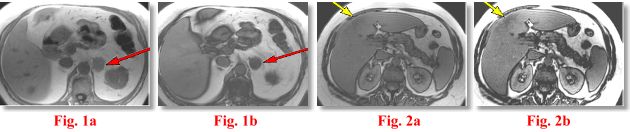

CASE #1: The patient in Fig. 1a-b presented with a left adrenal mass on a CT scan. The question was whether or not this represented a benign adenoma or other solid adrenal tumors including a malignancy.

CASE #2: The patient in Fig. 2a-b presented with a possible right lobe liver mass on a CT. The question was whether or not this represented a benign focal fatty infiltration (FFI) or a solid hepatic tumor including a malignancy.

PATIENT #1: CT images (not shown) demonstrated a low density left adrenal mass on patient #1 with some enhancement. The CT density on precontrast images was around 0 HU (near water density), which is typically seen with adenomas. The MR image (Fig. 1a) shows the mass to be of intermediate signal intensity on in-phase T1W images (red arrow), which is nonspecific. However, on out-of-phase images (Fig. 1b), the mass became darker, indicating the presence of fatty metamorphism typically seen with a non-functioning adenoma. Diagnosis of an adenoma can be comfortably made with this technique.

PATIENT #2: CT images (not shown) demonstrated an ill-defined low density are in the right lobe of the liver. A mass could not be excluded. The MR image (Fig. 2a) shows the area to be barely visible and of subtle low-to-intermediate signal intensity on in-phase T1W images (yellow arrow), which is nonspecific. However, on out-of-phase images (Fig. 2b), the area became darker, indicating the presence of fatty component typically seen with focal fatty infiltration (FFI).

DISCUSSION: Out-of-phase MR imaging relies on the fact that the protons in water and fat resonate at a slightly different frequency (220 Hz at 1.5 Tesla to be exact). This difference is exploited to cause the fat and water protons to be exactly “out-of-phase”, thus canceling each other out and causing a darker image. This is accomplished by varying the so-called echo-time (TE). At 1.5 Tesla, fat and water protons are “in-phase” at TE’s of about 0, 4.4, 8.8 msec, etc. and “out-of-phase” at TE’s of about 2.2, 6.6 msec, etc *. Out-of-phase MR images typically have a dark border around the organs (“boundary effect”) such as seen in Fig. 1b, 2b. Other fat-containing lesions can be diagnosed in the same manner. All the above MR images were obtained on AIC’s high-field Siemens Symphony utilizing ultrafast breath-hold scanning.